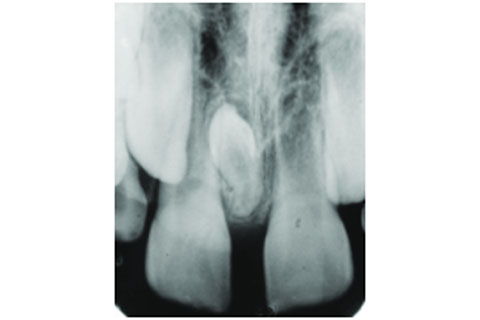

舉個例子,下X光圖病人門牙牙縫過大,想要箍牙改善外觀。豈知X光檢查發現兩隻牙齒中間骨頭內有多生齒,單純口腔內部觀測無法發現。需要手術拔除後才能進行治療。倘若無註冊牙醫進行檢查和監督治療,直接從坊間購買自助牙箍進行治療,恐怕這兩隻門牙也要鬆脫了。

自從隱適美Invisalign 專利權限過期之後,市面上多了很多不同牌子的透明牙箍或自助式箍牙,例如:Trioclear,SmileDirectClub,Zenyum 等等。在選擇牙箍牌子時,必須選擇由註冊牙科醫生全程跟進的品牌。要在醫生檢查過後,確保牙齒口腔健康的情況下才開始箍牙治療。舉個例子,下X光圖病人門牙牙縫過大,想要箍牙改善外觀。豈知X光檢查發現兩隻牙齒中間骨頭內有多生齒,單純口腔內部觀測無法發現。需要手術拔除後才能進行治療。倘若無註冊牙醫進行檢查和監督治療,直接從坊間購買自助牙箍進行治療,恐怕這兩隻門牙也要鬆脫了。